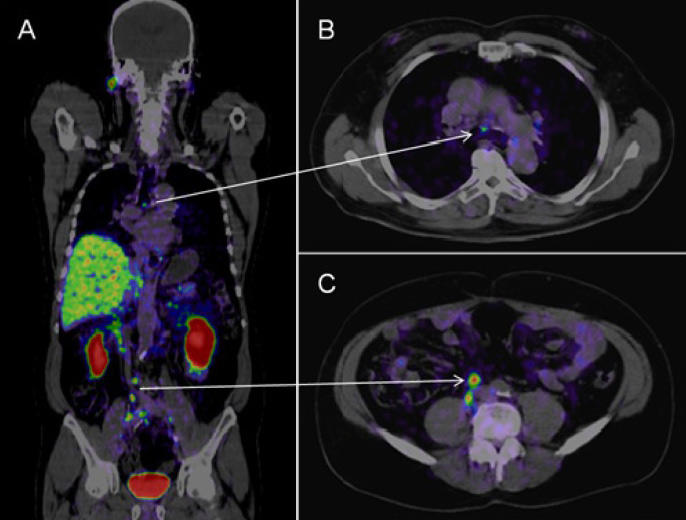

A través de un arduo trabajo, los equipos técnicos del Servicio de Salud Viña del Mar Quillota y del Hospital Dr. Gustavo Fricke avanzan satisfactoriamente en la aprobación del proyecto que permitirá contar con los recursos para la adquisición de un equipo de la más alta tecnología destinado a la realización de tomografías por emisión de positrones (PET), utilizando pequeñas cantidades de materiales radioactivos denominados radiosondas. Mediante la identificación de cambios a nivel celular, este equipo puede detectar manifestaciones tempranas de patologías del cáncer.

Respecto del modelo de gestión y de producción, se estima que anualmente se podrán realizar más de 3 mil exámenes y estudios de pacientes, cuyos procesos consideran, entre otras materias, detectar el cáncer y sus diagnósticos, determinar posibles metástasis, evaluar la efectividad del tratamiento, determinar si el cáncer ha vuelto luego del tratamiento y evaluar el pronóstico de la enfermedad.

De acuerdo a lo que indica la Dra. Christine Rojas, referente de Hemato Oncología del Hospital Dr. Gustavo Fricke, “esta tecnología es útil para los pacientes oncológicos en general. Cuando uno piensa en un PET CT, piensa en un escáner que no solamente ve una imagen, sino que ve si esa imagen que está metabólicamente activa o inactiva. El tejido tumoral tiene más ‘hambre’ por el azúcar que el tejido normal, por lo tanto, junto con hacer el escáner, se administra una glucosa, un azúcar radioactiva que es de lo cual comen las células. Por lo tanto, si hay un tejido que capta azúcar significa que está vivo. Entonces, si yo tengo un cáncer y tengo un ganglio, pero ese ganglio no está comiendo azúcar, significa que es solamente una cicatriz que está muerta, lo que implica que la persona no tiene cáncer. Por el contrario, si come azúcar, significa que sí tiene, por lo tanto, me permite saber cuán ramificado está el cáncer y además me permite, cuando termino la terapia, saber si la persona efectivamente se curó”.

Los exámenes de medicina nuclear brindan información de alta precisión que, por lo general, no se puede obtener con otros procedimientos de imágenes y presentan una mejor relación costo beneficio, permitiendo evitar las cirugías exploratorias. Mediante la identificación de cambios a nivel celular, las imágenes por PET pueden detectar la aparición temprana de la enfermedad antes de que sea evidente con otros estudios por imágenes.

Imagen referencial de examen Pet CT